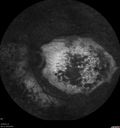

80 year old man Diagnosed at age 12 with retinitis pigmentosa. His central vision has been poor for a long time. He had surgery for nystagmus 3 times. He has worn glasses ever since he was 3 and he was bumping into walls when he was little. Night blindness was noticed by his mother at a young.

Mutations were confirmed in NR2E3 (Enhanced S Cone Syndrome)

VA OD HM; OS 6/200